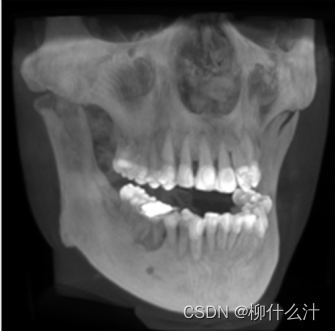

改造可以沿着手动或自动绘制的曲线进行。最常见的是沿牙弓绘制全景曲线,以生成一系列牙齿和骨骼的合成全景图(图00和01)。由于这些合成全景图像的厚度较小,通常不可能在一张图像中看到上下牙弓的情况。因此,通常需要为上、下牙弓分别绘制曲线(图02)。另外,可以计算出这些合成全景图的射线和,类似于从全景X光片上获得的图像。图23显示了不同厚度的合成全景堆叠的射线和全景图像。

沿着用户在轴向平面(左)绘制的曲线合成的全景图像(右)。

沿着与图20所示的曲线略微靠前或靠后的地方,额外的合成全景图像。

上颚(顶部)和下颚(底部)的合成全景图像。

不同厚度下的合成射线总和图像。